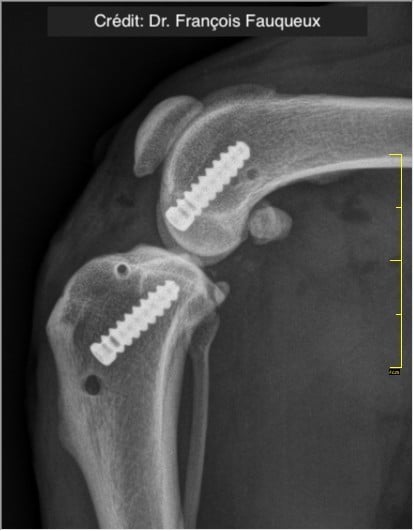

V případě více vazů kolene (kraniální, kaudální, kolaterální) je možné pomocí NOVALIG® anatomicky rekonstruovat každý vaz.

Radiologické snímky